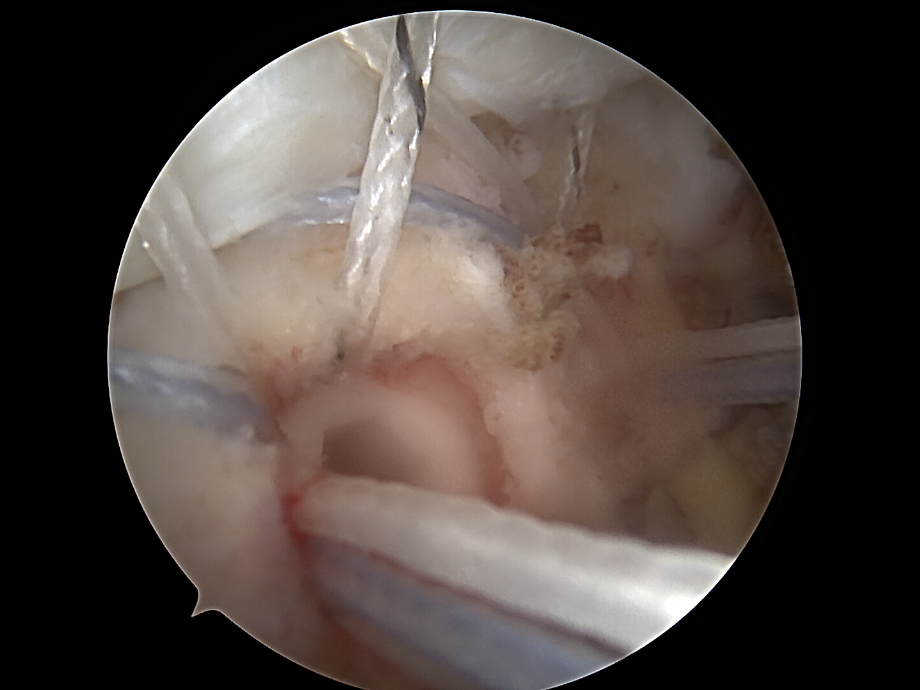

Arthroskopische Diagnostik

• Einführung der Arthroskopkamera über den hinteren (posterioren) Zugang).

• Inspektion des Glenohumeralgelenks und des Subakromialraums.

• Beurteilung der Rupturform: partiell, vollständig, zurückgezogen, degenerativ, traumatisch.

Darstellung und Mobilisierung der Sehnenstümpfe

• Débridement von degeneriertem Gewebe.

• Mobilisierung der rupturierten Sehne (meist Supraspinatus, ggf. Infraspinatus/Subscapularis).

• Darstellung des Ansatzbereichs am Knochen (Tuberculum majus/minus humeri).

• Glättung und Anfrischen des Footprints (Sehnenansatzstelle) zur Förderung der Knochen-Sehnen-Heilung.

rotatorenmanschette von dr. timmel von ortho-timmel.at